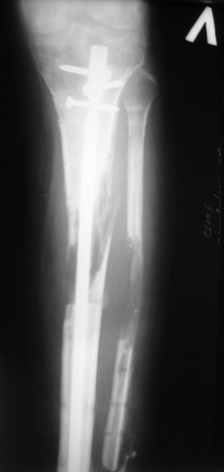

|  |  |  |  status localis на 14.11.08 (В ране визуализируется сухожилие.) | Больной А, 40 лет, находится в клинике с 15.10.08 с диагнозом: Сочетанная травма. Ушиб головного мозга лёгкой степени тяжести. Компрессионные переломы тел 12 грудного и 5 поясничного позвонков без неврологических осложнений. Закрытый внутрисуставной многооскольчатый перелом дистальных метаэпифизов обеих костей правой голени со смещением. Открытый внутрисуставной многооскольчатый перелом дистальных метаэпифизов обеих костей левой голени со смещением (см. Р-граммы). Хронический алкоголизм. Доставлен СМП после падения с 5-го этажа (не суицид). При поступлении состояние тяжелое. Глубокое оглушение. Дыхание самостоятельное, адекватное. Гемодинамика стабильная. По внутренней поверхности левой голени, в нижней трети, рвано-ушибленная рана 10-6 см, из раны выстоит проксимальный отломок большеберцовой кости, рана обильно загрязнена землёй. Интенсивная терапия в условиях реанимационного отделения, вытяжение за правую пяточную кость, параартериальная блокада обеих нижних конечностей, гипсовая лонгета на левую нижнюю конечность, ас-повязка на рану. Через 4 часа после поступления оперирован: после неоднократного промывания раны тёплой проточной водой с мылом, антисептиками, при ревизии определяется земля в канале проксимального отломка на глубину 3 см..., отсутствие надкостницы на концах дистального и проксимального отломков на 3 см. Удалено значительное количество мелких костных фрагментов, перемешанных с землёй, выполнена ПХО раны, резекция проксимального конца большеберцовой кости на 3,5 см, ЧКДО аппаратом Илизарова. Рана не ушивалась. В последующем перевязки раны с "Левомеколь", через 3 недели с момента травмы в ране определялись грануляции, нежизнеспособный конец дистального отломка. 10.11.08 ВХО раны, резекция дистального отломка на 3 см, перемонтаж аппарата наружной фиксации (см. Р-граммы). Отломки сближены на 2 см (остеотомию малоберцовой не делали). В настоящее время (5 сутки после операции) незначительное количество серозного отделяемого из раны, имеется дефект кости 4 см (см. Р-граммы). В последующем склоняемся к перемонтажу аппарата наружной фиксации, остеотомии малоберцовой кости в области повреждения, сближении отломков. По заживлению раны удлинение левой голени на 4 см. Однако, некоторыми высказывалось мнение о необходимости артродеза. Представляем рентгенограммы левой голени при поступлении, после повторного оперативного лечения и фото st.localis на 14.11.08. Будем очень благодарны за критику, комментарии, пожелания и мнения о дальнейшей тактике лечения.